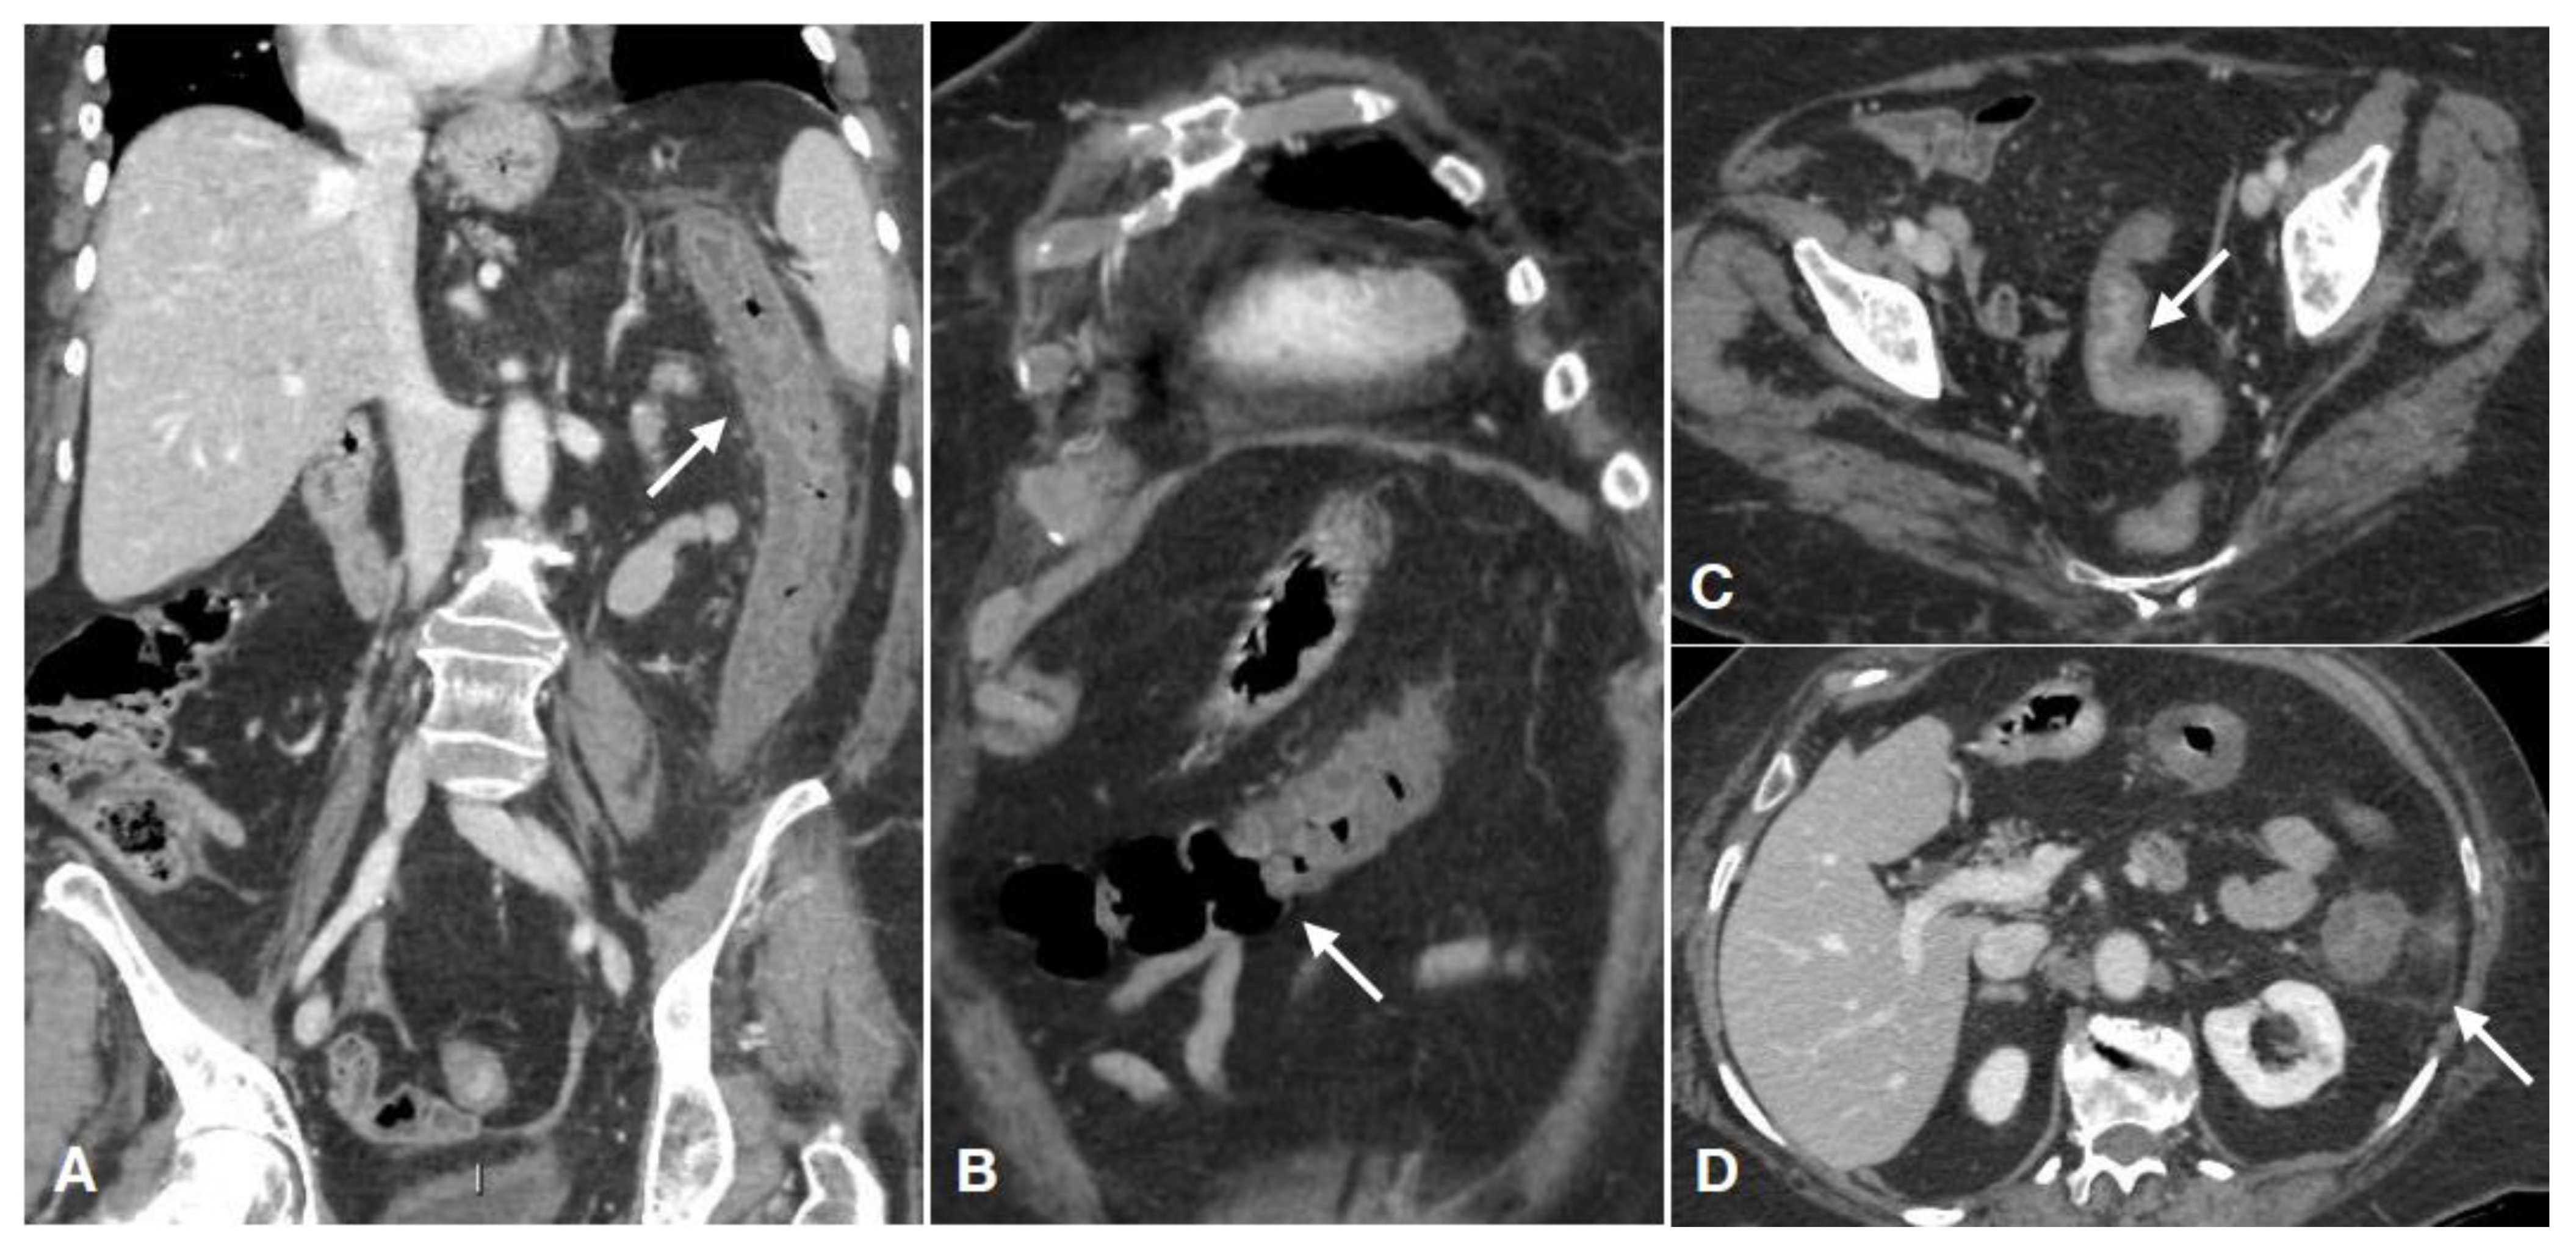

| Damage | Radiological Findings and Characteristics |

|---|---|

| Type of damage Arterial ischemic type (less frequent) Reperfusive type (more frequent) Venous congestion (rare) | Thin or “paper thin” colonic wall; |

| Unenhanced colonic wall at enhanced CT; | |

| Dilation of the lumen, only gas-filled; | |

| Wall pneumatosis; | |

| Pneumoperitoneum; | |

| Parenchymal ischemia of liver/kidney/spleen; | |

| SMA/IMA or relative branches obstruction; | |

| Peritoneal/retroperitoneal free fluid (late finding); | |

| Thickened colonic wall; | |

| Mucosal hyperdensity (“little rose” sign); | |

| Lumen caliber reduction; | |

| Stratified enhanced wall (“target sign”); | |

| Fat stranding; | |

| Pericolic fluid; | |

| SMV/IMV or relative branches obstruction; | |

| Bowel wall findings similar to the reperfusive type; | |

| Peritoneal/retroperitoneal free fluid | |